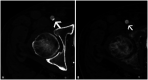

Photon-counting detector (PCD) CT is a new CT technology utilizing a direct conversion X-ray detector, where incident X-ray photon energies are directly recorded as electronical signals. The design of the photon-counting detector itself facilitates improvements in spatial resolution (via smaller detector pixel design) and iodine signal (via count weighting) while still permitting multi-energy imaging. PCD-CT can eliminate electronic noise and reduce artifacts due to the use of energy thresholds. Improved dose efficiency is important for low dose CT and pediatric imaging. The ultra-high spatial resolution of PCD-CT design permits lower dose scanning for all body regions and is particularly helpful in identifying important imaging findings in thoracic and musculoskeletal CT. Improved iodine signal may be helpful for low contrast tasks in abdominal imaging. Virtual monoenergetic images and material classification will assist with numerous diagnostic tasks in abdominal, musculoskeletal, and cardiovascular imaging. Dual-source PCD-CT permits multi-energy CT images of the heart and coronary arteries at high temporal resolution. In this special review article, we review the clinical benefits of this technology across a wide variety of radiological subspecialties.